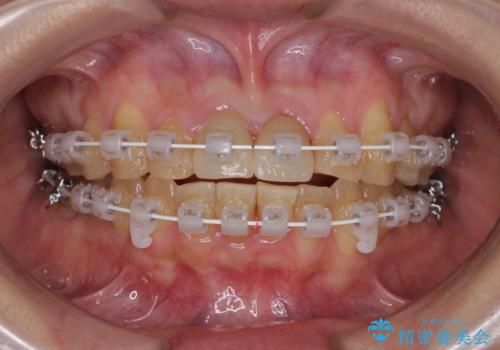

- 矯正装置

- 審美装置

- 治療期間

- 3年2ヶ月